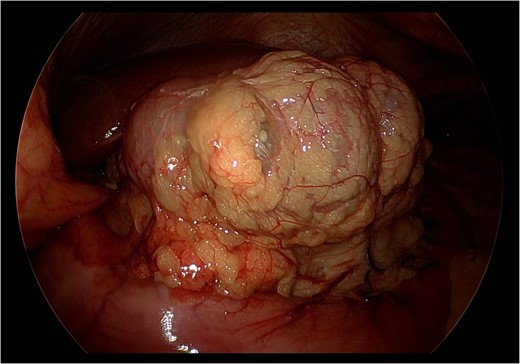

Upon laparoscopic exploration, the cecum was visualized herniating through the foramen of Winslow (Fig. 3), resulting in elevation of the portal structures and biliary compression. The gallbladder was distended with early signs of inflammation. There were no intraabdominal adhesions. Laparoscopic cholecystectomy was executed in standard fashion after obtaining the critical view of safety. Afterwards, using a combination of traction and pushing, the cecum was laparoscopically reduced from the lesser sac (Fig. 4). Although the cecum did not appear ischemic or necrotic, the highly mobile cecum was resected to prevent future volvulus, obstruction, or strangulation. All trocars were then removed, and pneumoperitoneum was released. A small upper midline incision was made, and the cecum and small bowel were extracorporealized. A stapled side-to-side, functional end-to-end, anti-peristaltic ileocolonic anastomosis was performed with 60 mm purple Endo-GIA staplers. With blunt dissection, the foramen of Winslow defect was gently widened to prevent future bowel strangulation. The midline fascia was closed with two running 1 Stratafix sutures. The skin was closed with staples and covered with an incisional negative pressure wound therapy vacuum.

Still photograph obtained during exploratory laparoscopy demonstrating complete reduction of the cecum from the lesser sac without signs of ischemia or necrosis.